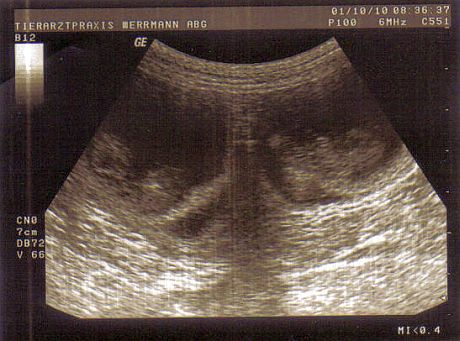

Hier sehen sie zwei Fruchtblasen mit den darin liegenden Welpen.